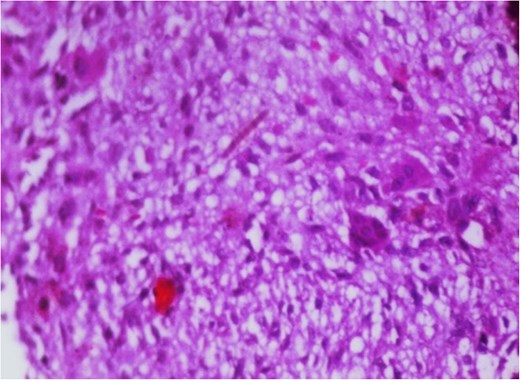

Additionally, magnetic resonance venography (MRV) confirmed a patent superior sagittal sinus with no encroachment of the lesion (Fig. 4). Differential diagnoses included dermoid cyst, eosinophilic granuloma, or benign fibro-osseous lesion. Surgical intervention involved en bloc excision under general anesthesia. A curvilinear incision was made over the mass, followed by subperiosteal dissection, which confirmed the lesion’s confinement to the diploë. Intraoperative frozen section analysis was not performed due to the lesion’s benign radiological features. Histopathological examination confirmed NOF, demonstrating ectodermal inclusion, cellular stroma of spindle-shaped fibroblasts arranged in a prominent storiform pattern, and scattered osteoclast-like giant cells. Notably, no evidence of mitotic figures, nuclear atypia, or necrosis was observed (Figs 5–7). The margins were free of lesional tissue. Postoperatively, the child resumed oral intake within 4 hours and was discharged on postoperative day 2 with analgesics. At the 6-month follow-up, the wound had healed without complications, with no recurrent lesion.

Photomicrograph in a case of NOF showing osteoclast-like giant cells, H&E original magnification × 400.